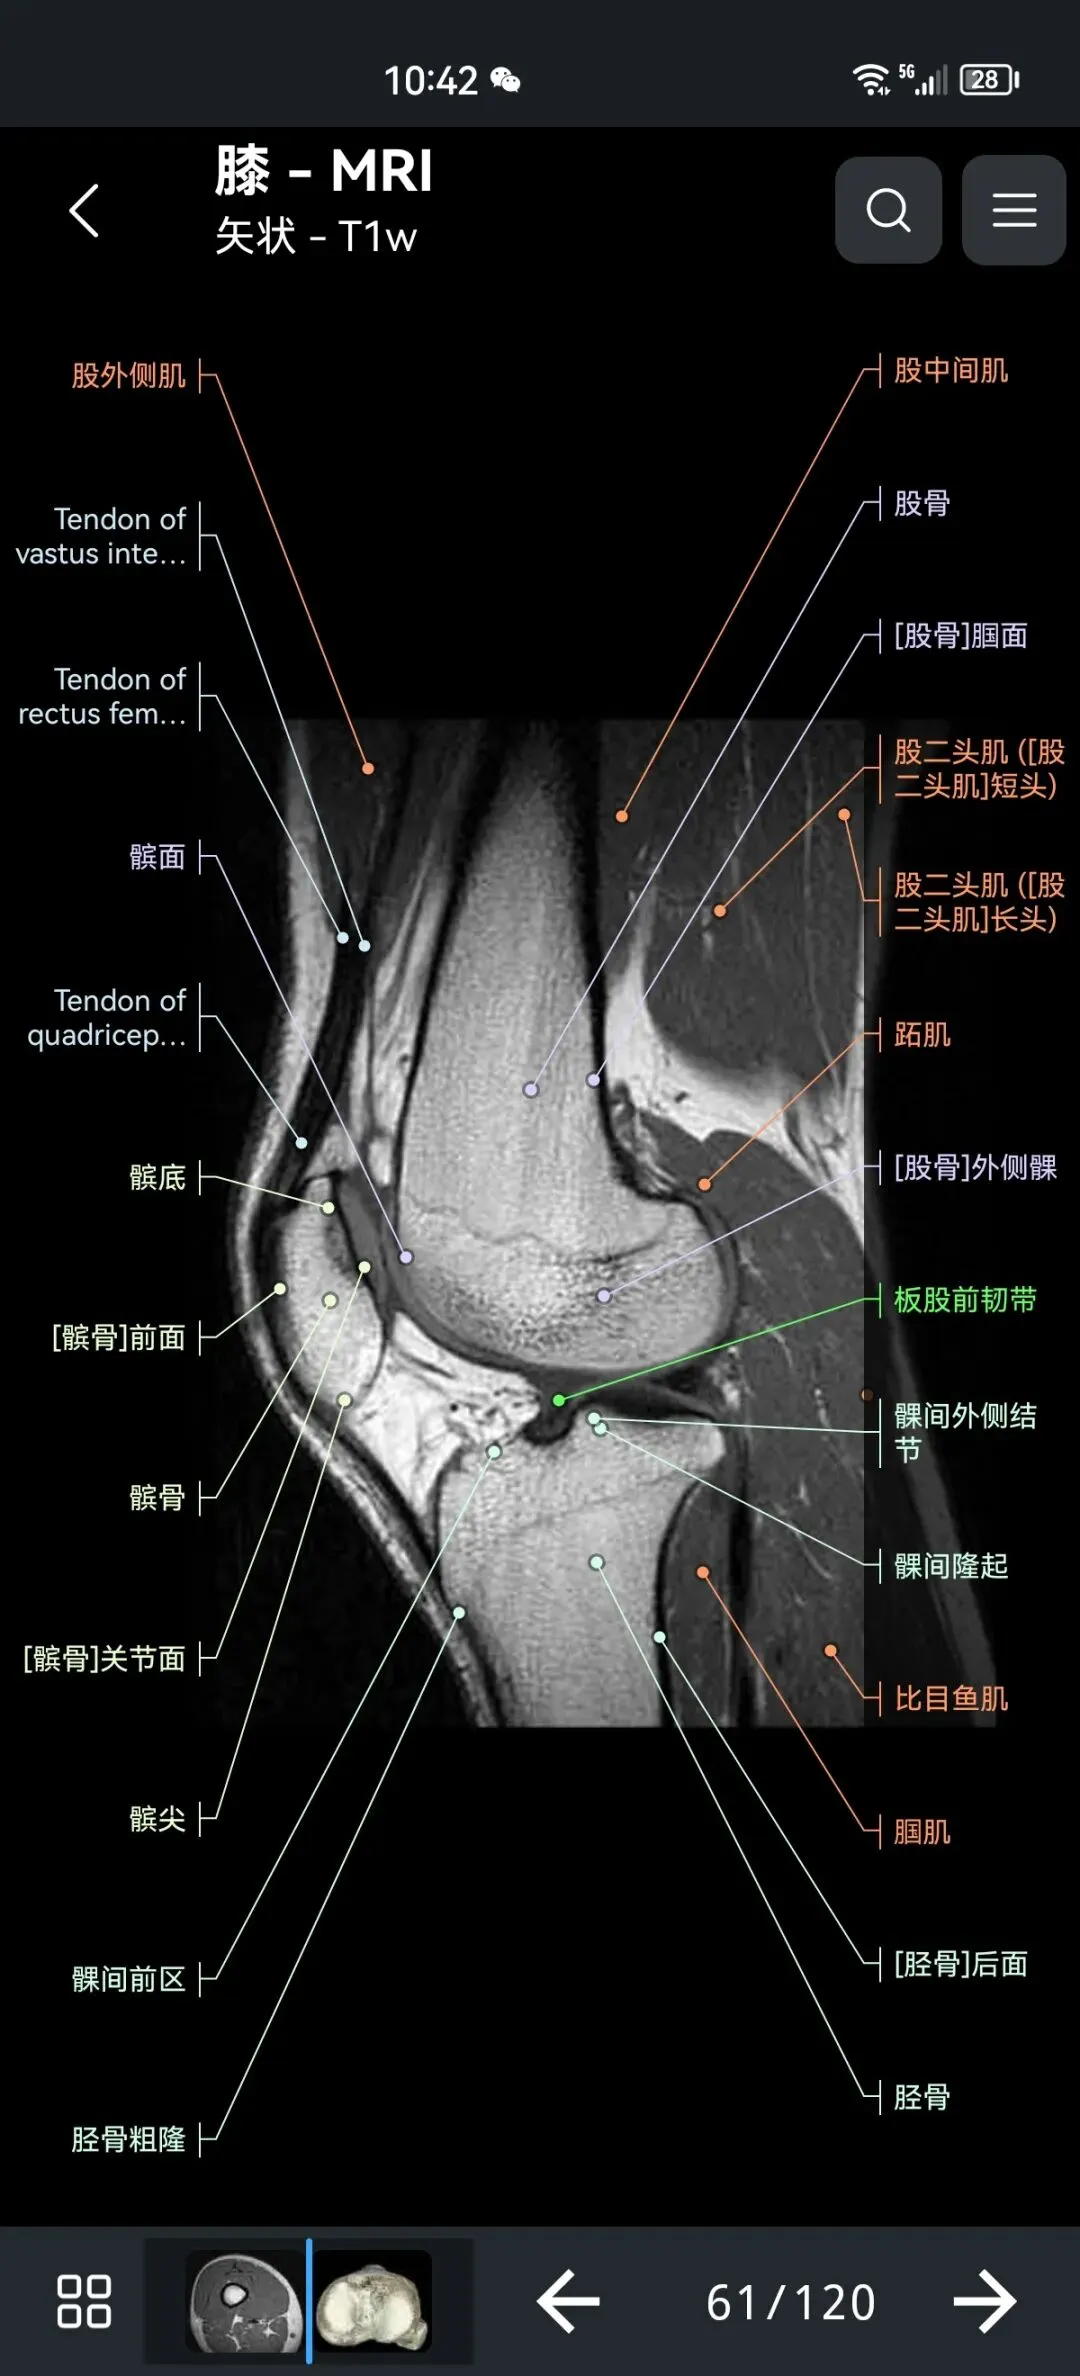

覆盖了X光、CT、MRI、断层大体解剖、核医学、介入造影、医学插图等多个模块,覆盖全身各个系统的影像解剖(正常解剖结构,无病例),其中的解剖结构高达87万个,结构标注超精细,超高清图像,历时两年研发设计完成✅。